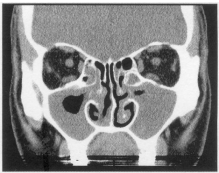

72 16 歲男孩,主訴鼻塞、濃稠鼻涕已經超過一年。根據此張 plain CT 片,最可能的診斷是:

(A) Chronic rhinitis (B) Chronic paranasal sinusitis (C) Fungal infection in the paranasal sinuses (D) Tumors in the paranasal sinuses